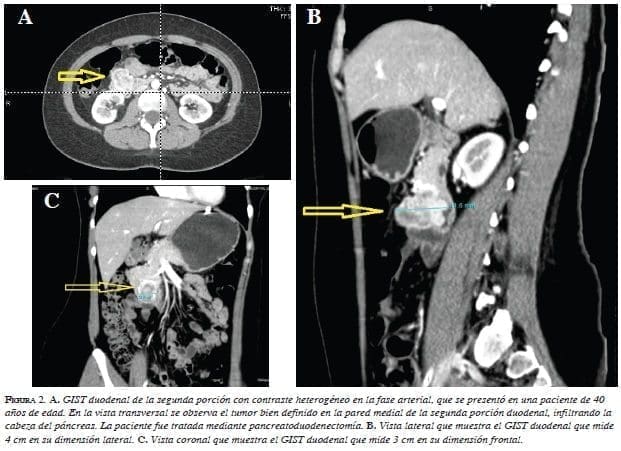

El estudio radiológico con mayor disponibilidad en la actualidad para identificar y diagnosticar GIST, es la tomografía computadorizada (TC). Prácticamente todos los GIST duodenales son detectados con TC 17,18,29. Los GIST son tumores hipervasculares que en imágenes muestran un intenso contraste en la fase arterial 15. La mayoría muestra un contraste homogéneo y aparecen como masas endofíticas o exofíticas bien definidas 29-33. Los tumores pequeños se muestran como masas homogéneas bien delineadas ovaladas o redondas contrastadas moderadamente 29,31,33-36 (figura 1). Los GIST grandes pueden presentar ulceración de la mucosa, se observan bien contrastados, bien delimitados, lobulados y heterogéneos, pueden presentar necrosis central, cavitación, líquido y crecimiento endoluminal y extraluminal 7,17,29,30, 31,33,37 (figuras 2 y 3).

Los criterios tomográficos para la descripción y el registro de GIST fueron establecidos por Burkill, et al. 31,32 (tabla 5). Los GIST evidentemente malignos presentan metástasis hepáticas o invasión local de los tejidos y órganos circundantes 29-37.